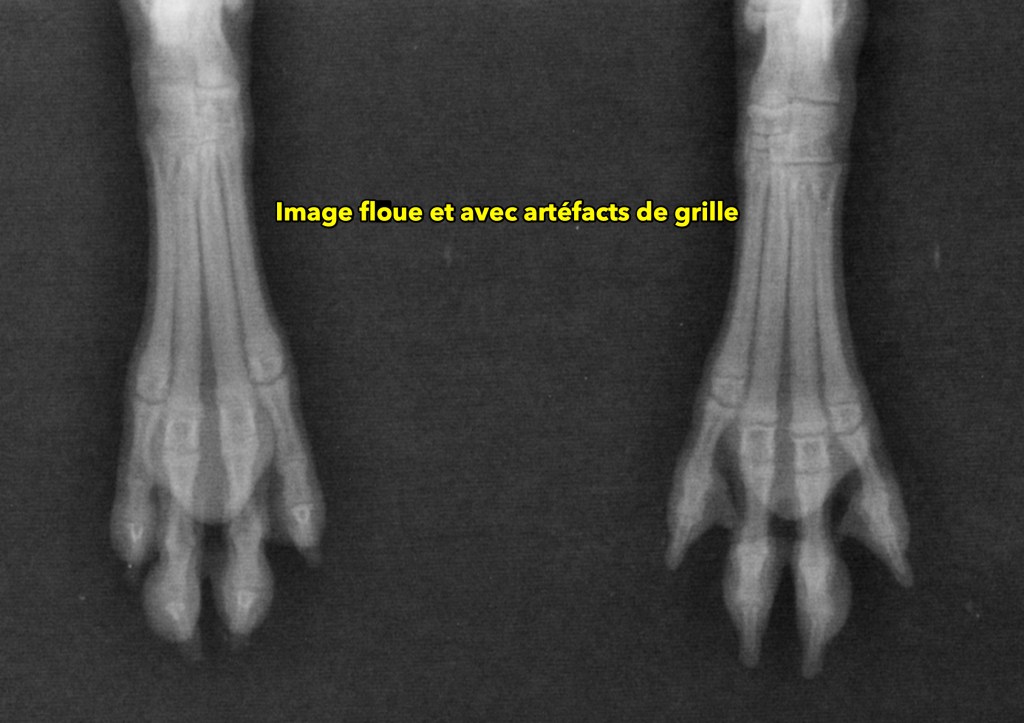

Outre ce positionnement, il faut aussi souligner l’importance de la qualité des images numériques reçues. En effet, ce n’est pas parce que l’animal est bien positionné que l’image radiographique sera forcément optimale pour l’interprétation. La perception subtile des structures normales et anormales peut être grandement affectée lors d’exposition inadéquate ou lorsque le système numérique (ou l’appareil qui émet les rayon-X) n’est pas optimal (problème de calibration, fluctuation de courant, plaque à faible sensibilité aux rayons-X ou à faible résolution).

Les images ci-bas suivantes mettent en relief certains de ces problèmes. Une sous-exposition radiographique (ex. kVp et/ou MAs trop bas pour la région imagée) aura pour effet de limiter la pénétration des structures plus denses (ex. os, voir image #1). Aussi, un nombre insuffisant de rayons-X atteignant le détecteur (plaque numérique) produira davantage de bruit sur l’image qui sera alors affectée. Le résultat sera une image plus granulaire, similaire à si vous aviez pris une photo de nuit avec votre vieil iPhone. Une telle granularité peut aussi apparaître si la plaque numérique est peu sensible (voir image #2), même à exposition adéquate.

Une image floue peut s’expliquer par un mouvement du patient durant la période d’exposition, mais aussi par un capteur à faible résolution (voir images #7 et #8)

Finalement, plusieurs artéfacts peuvent aussi affecter la qualité des images. Ces artéfacts qui apparaissent souvent comme des lignes ou des petits points blancs (voir image #2) peuvent provenir de débris denses à l’extérieur du patient (ex. sur la table), de débris dans un lecteur de cassette numérique, d’un bris dans le capteur numérique (plaque ou cassette) ou d’une autre cause.